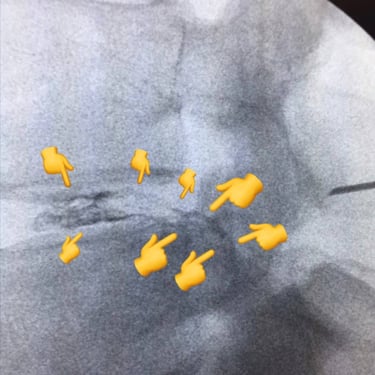

This young lady had a disc herniation at T12-L1 and was seeking treatment due to localized and radiating pain. In the images below:

The patient during the Discogel injection, the site of injection, immediate CT scans after Discogel injection, and a picture of the patient 8 years after Discogel injection. She is now a professional athlete, with her pain issues resolved